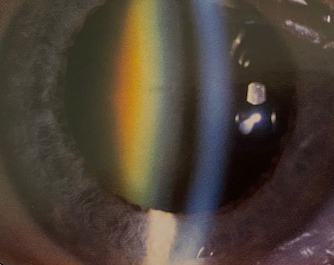

De ooglens is normaal doorzichtig en gelegen achter de pupil. Wanneer de lens troebel wordt (leeftijd, medicatie, diabetes, ongeval, . ) spreekt men van cataract.

Nucleaire cataract